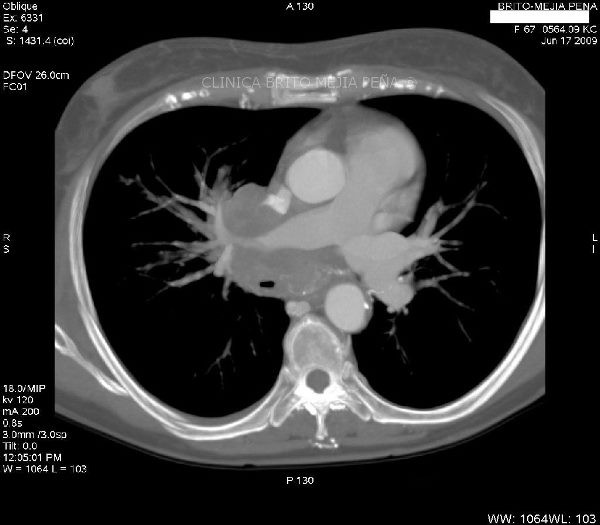

Aneurisma Aorta Ascendente